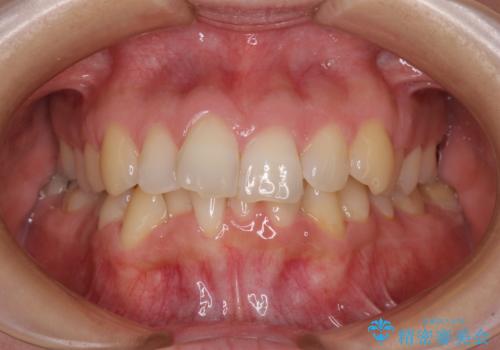

[ マウスピース矯正 ] 出っ歯に見える前歯を改善したい

![[ マウスピース矯正 ] 出っ歯に見える前歯を改善したいの症例 治療前](https://seimitsushinbi.jp/wp/wp-content/uploads/2023/10/IMG_6858-500x350.jpg?v=1697014973)